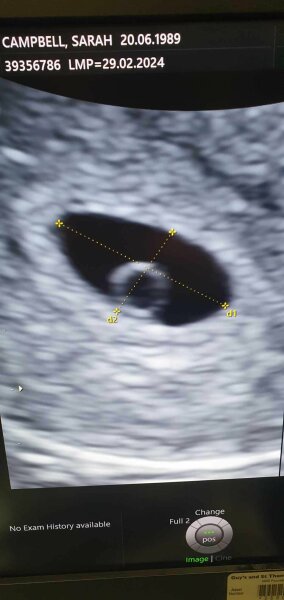

attached the pic she did say sometimes twins can share one egg yolk though

@Lauren0506 I had mine 5+5 and saw the 2 sacs back 24th April where ill be 8 weeks hopefully see more then this is via epu, mine was to rule out ectopic as had strange pains